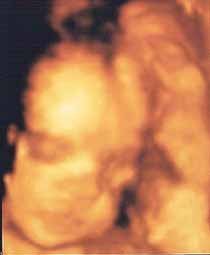

Inauguramos hoy nueva sección. “La foto de tu bebé” se estrena con la imagen en tres dimensiones de María Paula dentro del vientre de su madre.

Es increíble cómo apenas con 24 semanas de gestación se puede apreciar perfectamente la carita y los rasgos de la bebé.

Seguro que ya le habrán encontrado parecidos en la familia.

¡Enhorabuena! Esperamos la feliz noticia del nacimiento y, por supuesto, una foto fuera del vientre.